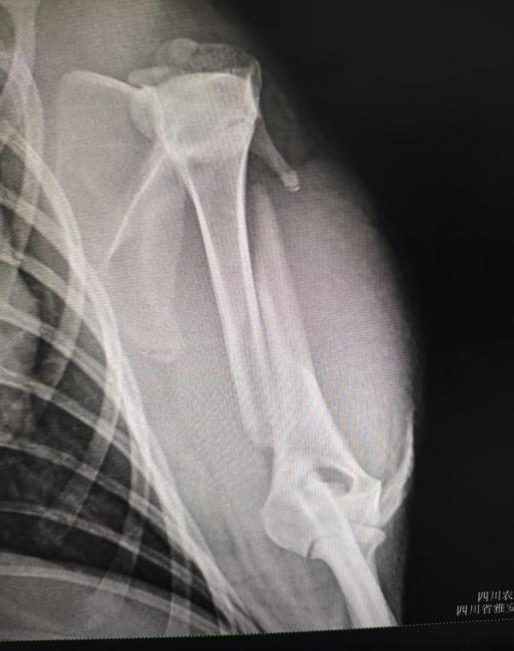

手术前左前肢腹背位X光

手术团队由bat365官方网站教学动物医院院长沈留红、动物外科专家石先鹏、动物内科专家巫晓峰、医生陈善瑜和罗皓、麻醉医生邓聪辉、手术助手王郡东、助理唐清婷、张涵艺、钱琳、王均、李鑫等组成,并与动物园动物疾病预防组刘俊卿副经理团队一道组成会诊专家组,确定麻醉和手术方案。外科专家石先鹏凭借丰富的经验和精湛的技术,对水豚肱骨进行了精确的复位和固定。手术全程在严格的无菌条件下进行,确保了安全性和成功率。